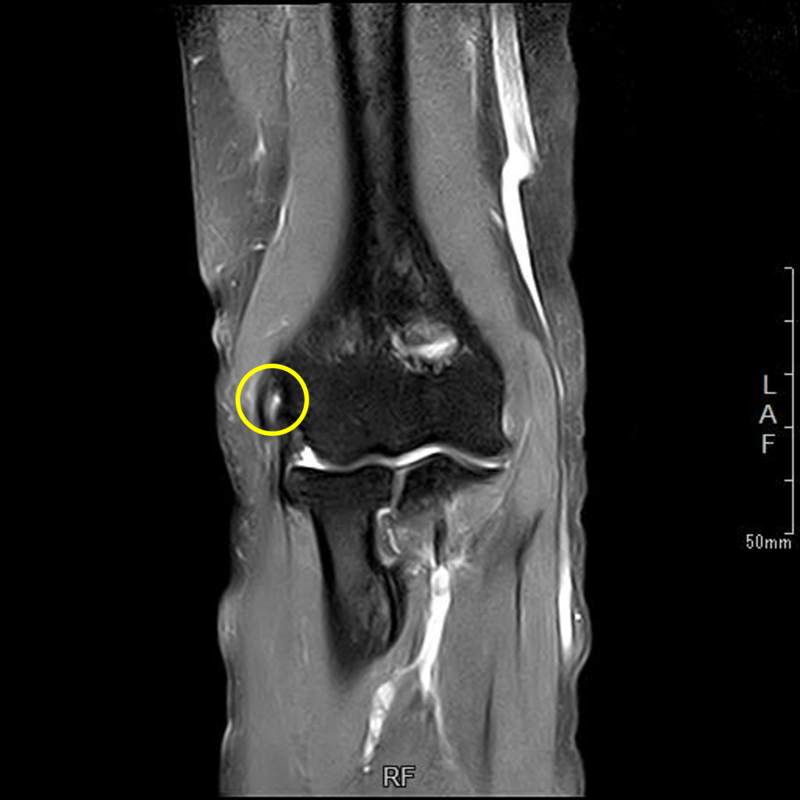

肘の離断性骨軟骨炎(以下:OCD:osteochondritis dissecans)は上腕骨小頭という部位に好発することが多いです。

OCDは成長期の代表的なスポーツ障害であり、野球などといった投球・投擲動作を行うスポーツ選手で投球側に発生することが多いです。大半は10-12歳で発症し成長期における有病率は2-3%と頻度は少ないが進行するとスポーツにみならず、日常生活お支障をきたすことが多い怪我です。そのため、早期発見・早期治療が重要となります。

OCDを発見するにはレントゲンや超音波検査で上腕骨小頭軟骨下骨の状態を観察します。

軟骨下骨の不整像が軽微か不明の場合はMRI検査を行いOCDの確定診断を行います。

症例提示

12歳・男性・スポーツは野球(週2回/4年間)

2024年3月頃から外傷誘因なく疼痛出現。

2024年4月上旬、他院受診して超音波検査で軟骨が剝がれていると診断を受けたが経過観察のみ。

2024年5月、当院受診。レントゲン撮影をして離断性骨軟骨炎と診断されてリハビリ開始。

リハビリでは、徒手療法(マッサージ)・運動療法(筋力トレーニング ストレッチ)・物理療法を実施していましたが、

疼痛消失には至らず、組織修復を目的に体外衝撃波を実施しました。

体外衝撃波(拡散型圧力波治療)は、週1回の頻度で3回実施しました。

現在は、リハビリテーションでトレーニング継続中です。